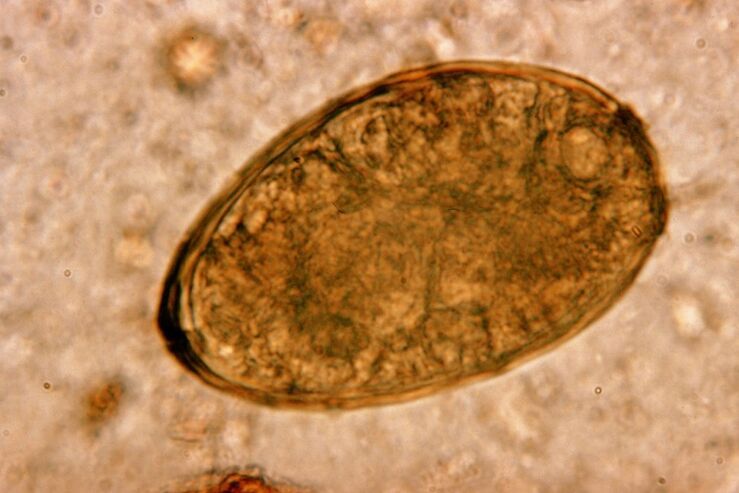

Οι στρογγυλοί σκώληκες ζουν και αναπαράγονται στα έντερα. Η μόλυνση με αυτά συμβαίνει μέσω αυγών που εισέρχονται στο σώμα με τροφή ή από χέρια και αντικείμενα που χρησιμοποιεί ένα μολυσμένο άτομο. Χώμα, φρούτα, λαχανικά, κακώς μαγειρεμένο κρέας και ψάρι - όλα αυτά μπορούν να εισάγουν αυγά ελμινθών στο ανθρώπινο σώμα.

Μόλις εισέλθουν στο γαστρεντερικό σωλήνα, τα αυγά των στρογγυλών σκουληκιών, υπό την επίδραση των δικών τους ενζύμων και του πεπτικού υγρού, αποβάλλουν το κέλυφός τους, μετατρέποντας σε προνύμφες. Τα τελευταία είναι προικισμένα με την ικανότητα να διεισδύουν μέσω του εντερικού τοιχώματος στην κυκλοφορία του αίματος. Μετά από αυτό μεταφέρονται από το αίμα σε όλο το σώμα - φτάνοντας στο συκώτι, την καρδιά, τους πνεύμονες και την αναπνευστική οδό.